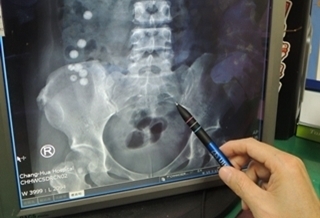

(優活健康網記者林奐妤/綜合報導)小腸長出一根避雷針?81歲的黃姓老翁有失智症,某日右下腹劇痛就醫。家人也不知怎麼造成,經回想才想到3天前曾吃過魚。因為老翁失智言詞反覆,但X光片看不出明顯異狀,電腦斷層才發現疑似有根異物穿刺小腸,緊急手術果然發現一根魚刺穿破小腸,如直立的避雷針。因為延宕3天才就醫,該處小腸化膿感染,切掉20公分小腸,若再拖延甚至可能引發敗血症送命。失智導致進食感知能力較差 吞進4公分魚刺衛福部彰化醫院一般外科主任余明昌表示,異物應是魚刺,穿過小腸引起腸液外漏,還出現腹膜炎症狀,只得緊急手術。打開腹腔,赫然發現小腸被一根約4公分的魚刺穿透,出現如避雷針畫面。該處小腸已化濃,無法局部修補,只好將感染的20公分小腸切除,再進行截斷處重接的吻合手術。小腸全長約400公分,主要對食物進行消化及吸收,少了20公分影響不大。一般若外來異物刺穿小腸,會造成腸液流出,肚子很痛,變成腹膜炎,若不馬上處理,還可能演變成敗血症,有生命危險。上述個案或許2至3天前就開始痛,但病人失智感知能力不足,造成延宕。所幸還能及時手術,黃姓老翁住院12天後出院。老年人吃魚 烹調大塊無魚刺搗碎後再吃如果魚刺細小根本穿不透小腸。但該魚刺長達4公分,照理說進到嘴中不難發現,進入喉部也應該有感覺,但病人完全不知情,應該是年紀大又失智導致嚼食敏感度大幅退化。老年人吃魚,最好烹調大塊無魚刺的魚種,搗碎後再給老人家吃會比較安全。臨床上吞食異物的病人以精神疾病患者和受刑人最多,但老人家因為各項功能退化,誤食異物較嚴重,以魚刺和雞骨頭情況最多。余明昌主任強調,如果異物位置在內視鏡可取出的食道、胃、直腸等處就直接以內視鏡取出,如果已經到了小腸,通常可以從肛門排出。但如果產生腹痛或觀察3天還無法排出,就得要手術取出,不然一旦引發腹膜炎,就有敗血症的可能。